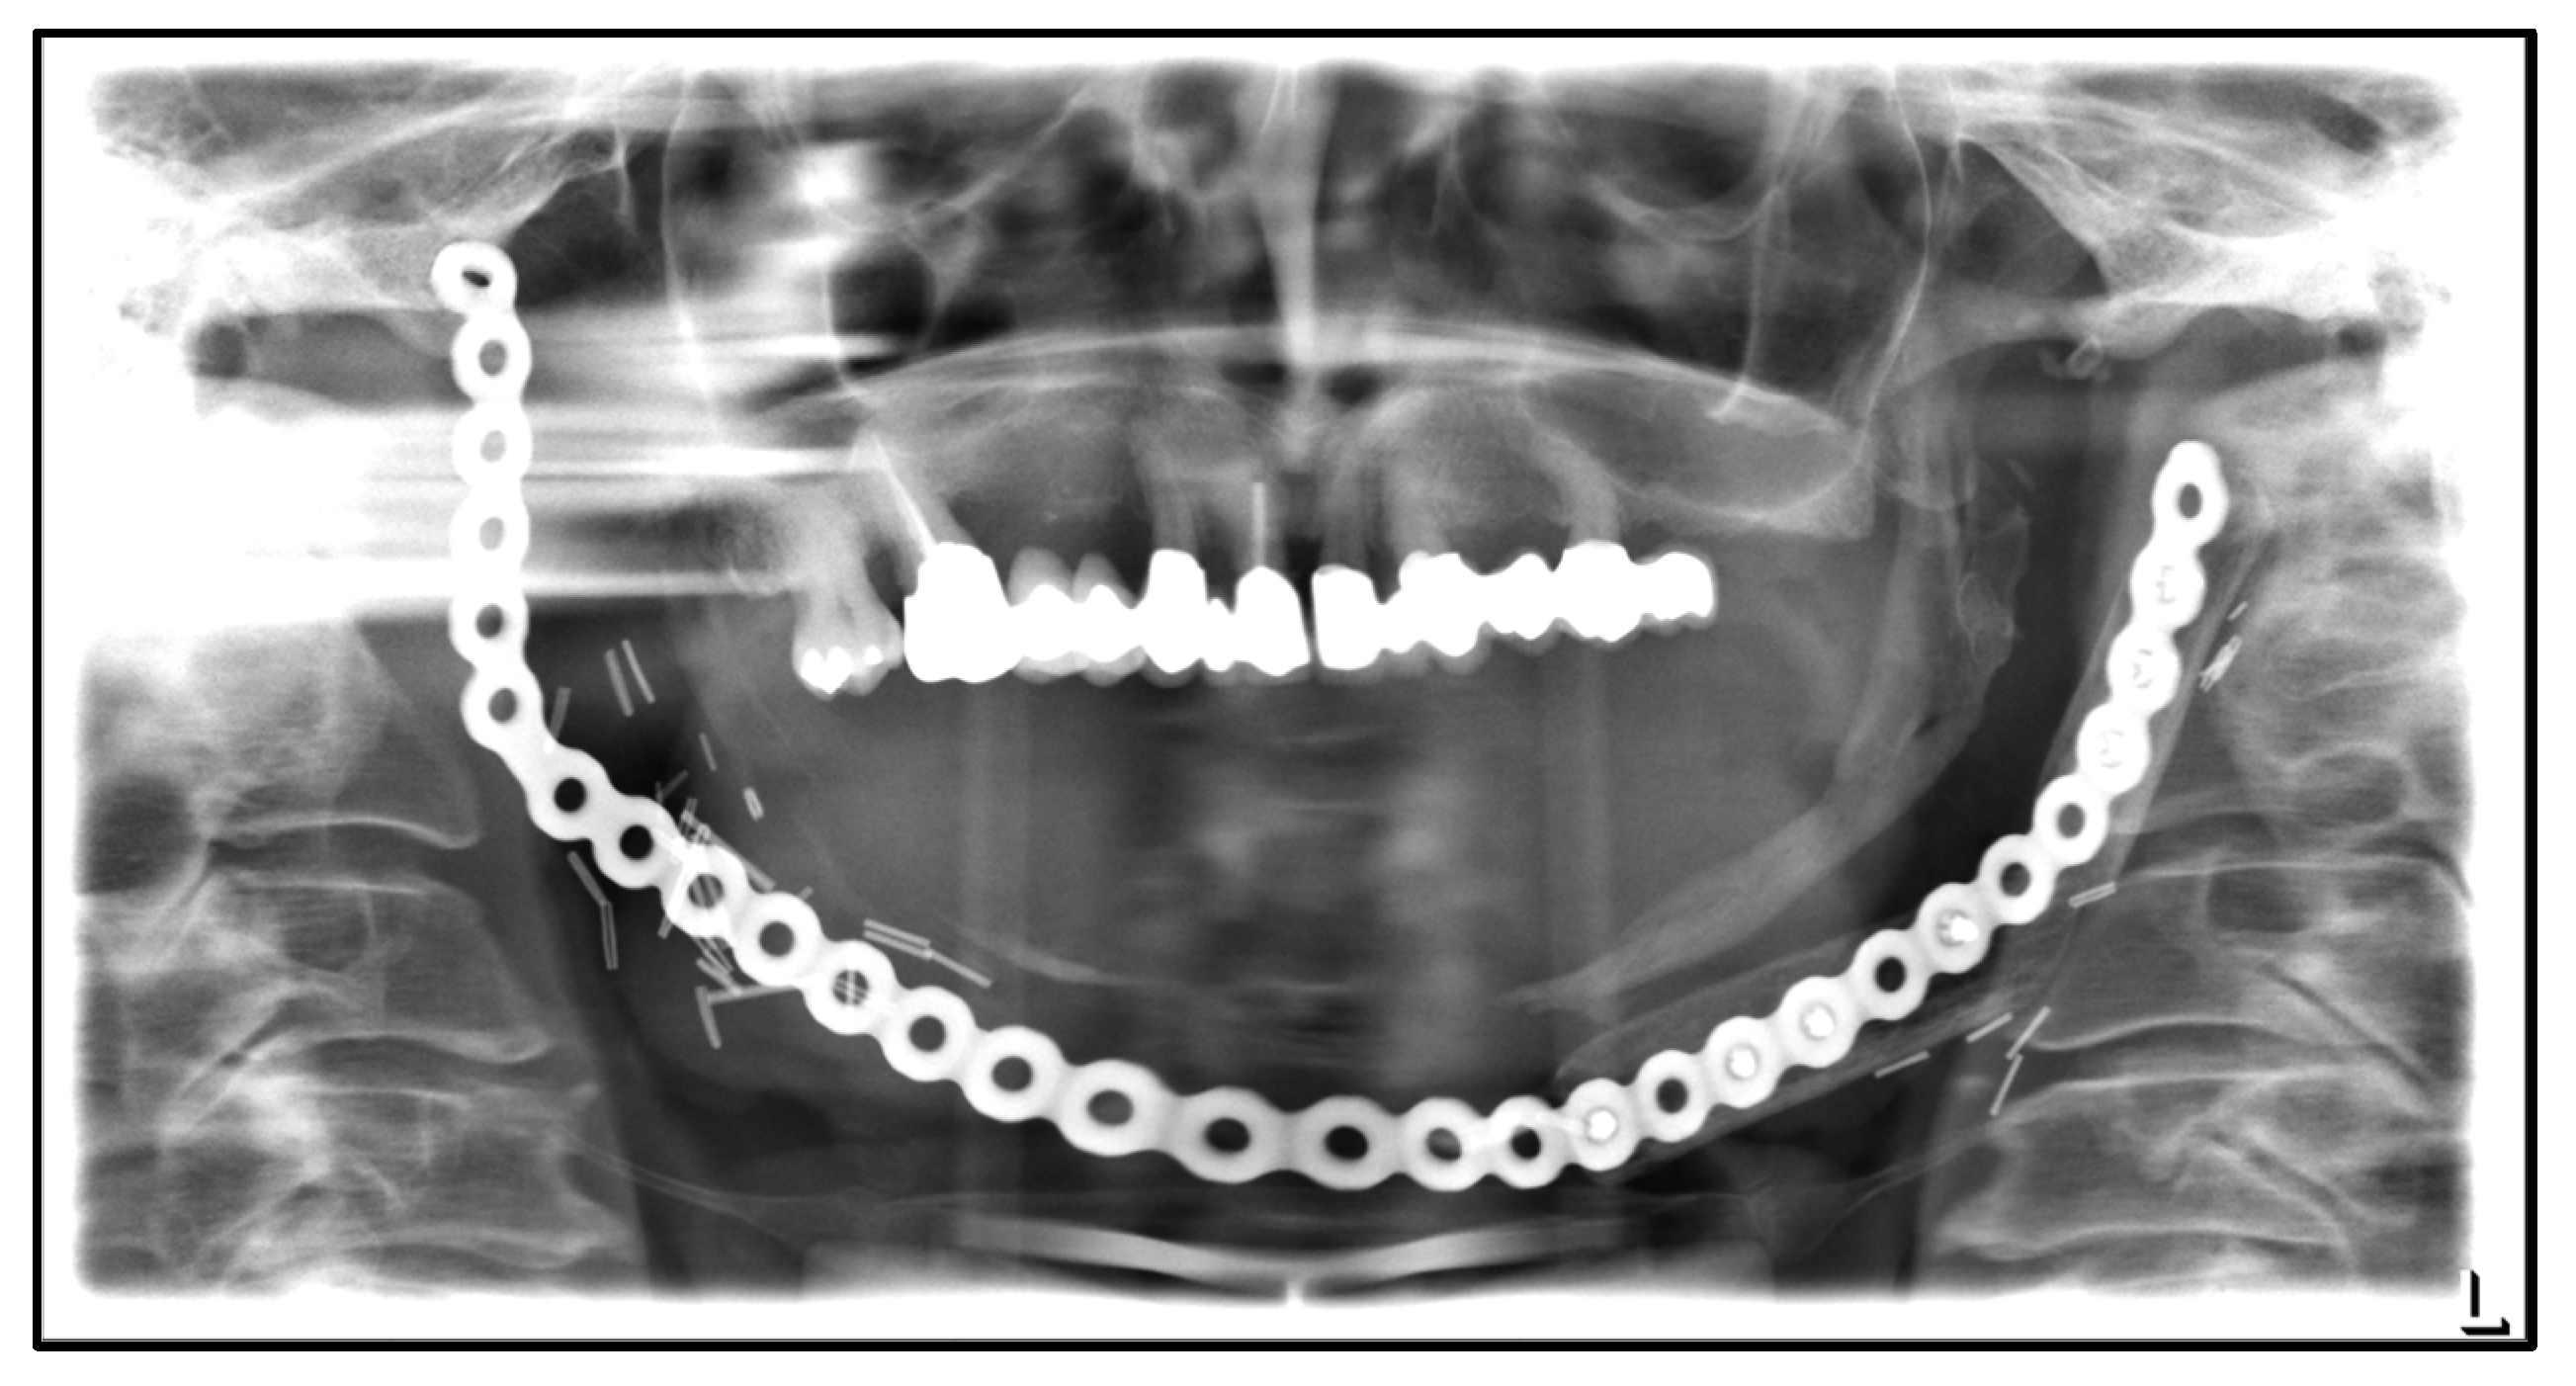

| September 2022: | Partial mandibular resection from the left mandibular angle to the right mandible, including the right temporomandibular joint, CAD/CAM-guided reconstruction with a bilateral free scapula flap with skin island, and patient-specific plate. In the course:

| April 2020: | Partial mandibular resection from the left to the right mandibular angle, CAD/CAM-assisted reconstruction using a free fibular graft and PSI, temporary tracheostomy. In the course: development of aspiration pneumonia treated with piperacillin and tazobactam 4.5 g for 8 days. |